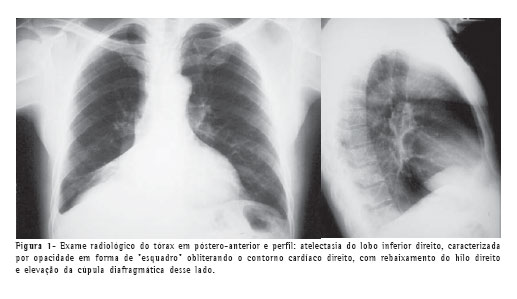

As radiografias do tórax nas incidências póstero-anterior e perfil evidenciaram sinais de redução volumétrica do lobo inferior direito, com borramento do contorno cardíaco desse lado (Figura 1).

A tomografia computadorizada de tórax confirmou a atelectasia e mostrou pequena lesão calcificada em luz de brônquio no lobo inferior direito (Figura 2), além de bronquiectasias com provável impactação mucóide no lobo pulmonar colapsado.